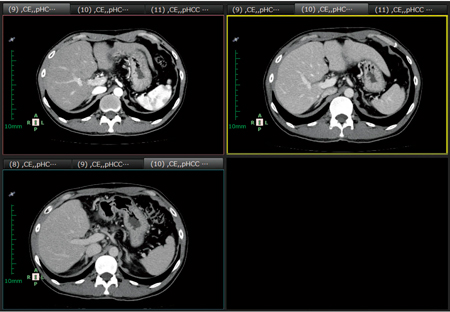

図2 タブを使った読影

「複数回の上腹部ダイナミック造影検査を比較する」といった,多くのシリーズを検討する必要がある状況でも,同一検査のシリーズを「動脈相・門脈相・遅延相」の順に重ねておくことで,整理が容易である。あらかじめこのような形のハンギングプロトコルを作成することも可能。